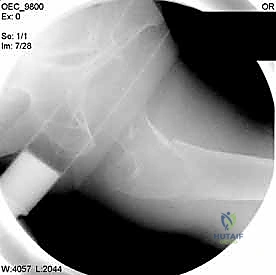

2. الرد المغلق تحت جهاز الأشعة (Closed Reduction)

قبل إجراء أي شق جراحي، يقوم الدكتور هطيف بسحب الساق وتدويرها بمهارة فائقة لإعادة العظام المكسورة إلى مكانها الطبيعي (المحاذاة التشريحية). يتم التأكد من ذلك باستخدام جهاز الأشعة السينية المتحرك داخل غرفة العمليات (C-Arm Fluoroscopy). هذه الخطوة حاسمة، فالرد الجيد يعني التئاماً ممتازاً.

مجموعة من الصور الإضافية التي توضح مراحل دقيقة من العمل الجراحي المعقد الذي يجريه الأستاذ الدكتور محمد هطيف لضمان أعلى درجات الدقة الميكانيكية الحيوية: